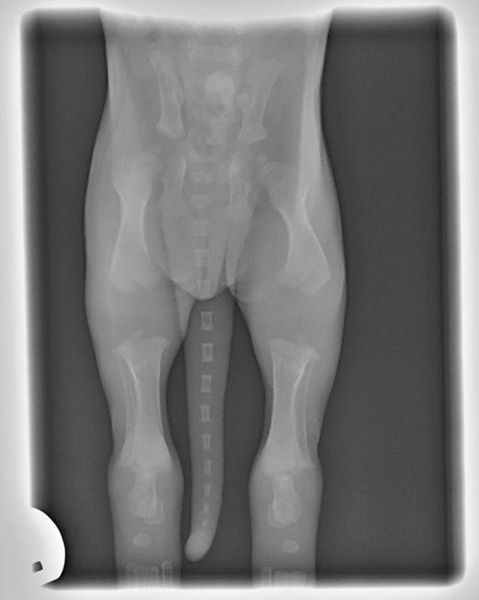

This is an X-ray of a puppy at 2 weeks old - just look to see how far the bones have to grow to just become proper bony joints, let alone become strong articulating joints that have correct feedback into the brain... this is why it is imperative that we don't over-exercise our puppies, and certainly not jump them or train them too hard before they are fully developed.

This is different age categories for different breeds, and if the dog has had any specific problems during it's puppyhood.

Please be careful at this stage so the dog's joints will last well as they age!